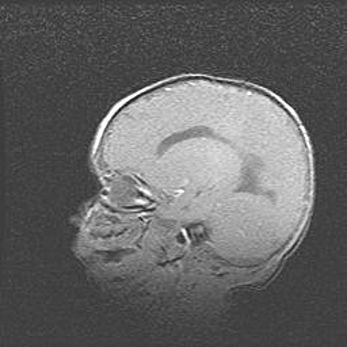

Аномалия Денди-Уокера. Признаки гипоплазии мозолистого тела.

Возраст: 5 месяцев 3 дня

Вес: 5550 г

Пол: мужской

Окружность головы: 39 см

Срок гестации: 40 недель

Аномалия Денди-Уокера – это порок развития головного мозга, для которого характерна триада симптомов: гипотрофия или аплазия червя мозжечка и/или полушарий мозжечка, расширение четвёртого желудочка с формированием ликворной кисты задней черепной ямки, гипертензионная гидроцефалия различной степени.

Гипоплазия мозолистого тела относится к дефектам внутриутробного этапа развития мозговой ткани, возникающим в процессе закладки структур головного мозга, что происходит на начальных этапах развития эмбриона.